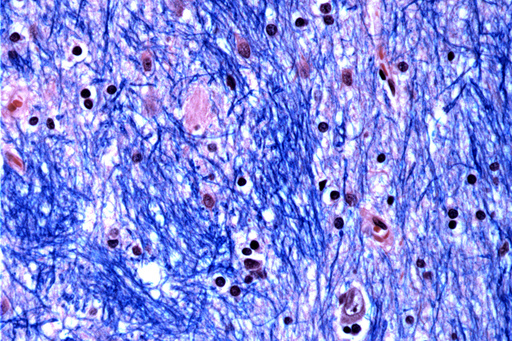

Scientists at the Broad Institute of MIT and Harvard, McLean Hospital in Massachusetts and Harvard Medical School studied brain tissue donated by 53 people with Huntington’s and 50 without it, analyzing half a million cells.

They focused on the Huntington’s mutation, which involves a stretch of DNA in a particular gene where a three-letter sequence – CAG – is repeated at least 40 times. In people without the disease this sequence is repeated just 15 to 35 times. They discovered that DNA tracts with 40 or more such “repeats” expand over time until they are hundreds of CAGs long. Once CAGs reach a threshold of about 150, certain types of neurons sicken and die.